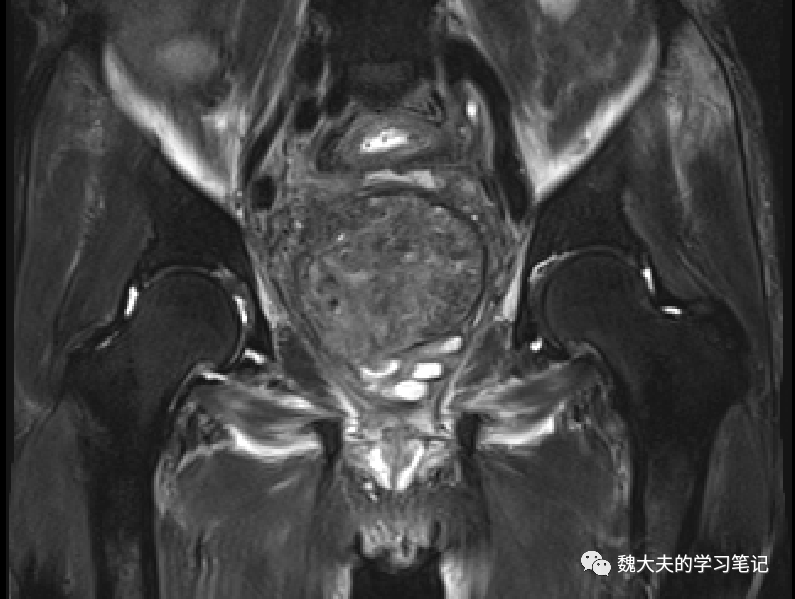

影像学资料:

图片

术前CT增强提示直肠乙状结肠占位,侵犯前列腺及膀胱底部,双肾盂扩张,输尿管积水

术前 MR检查见直肠巨大占位